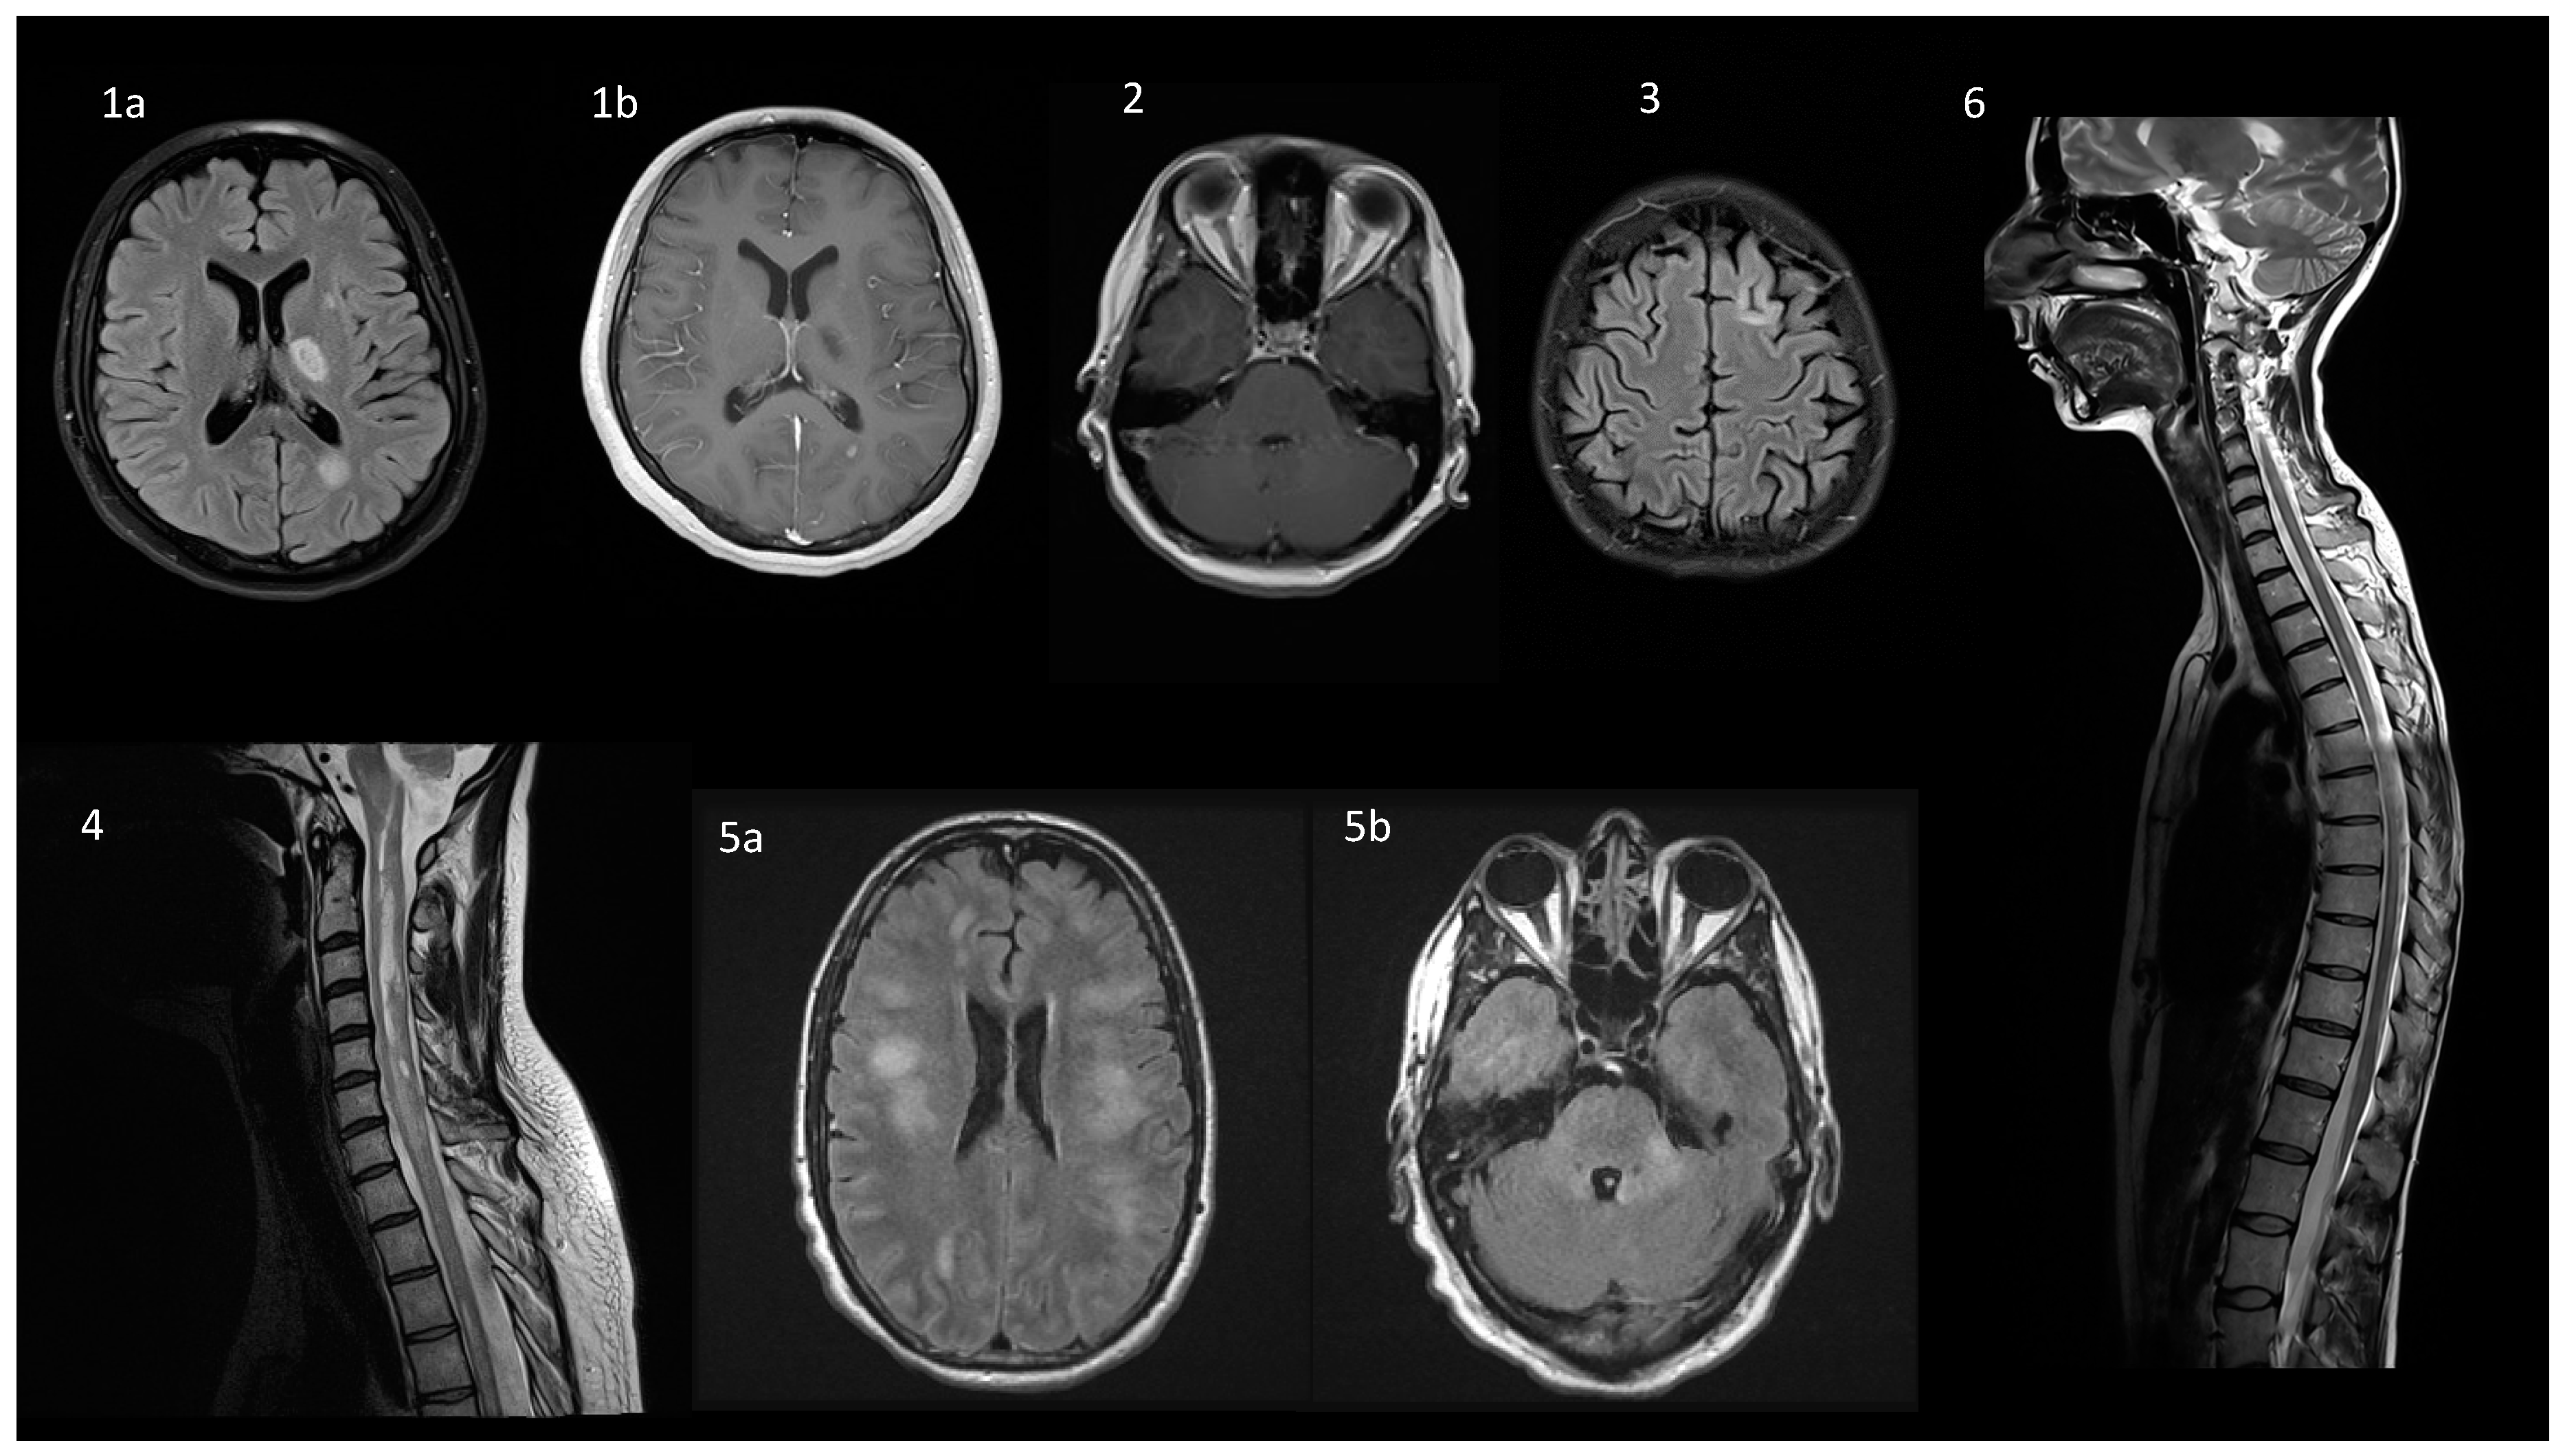

6. Neuroimaging

| MRI image |